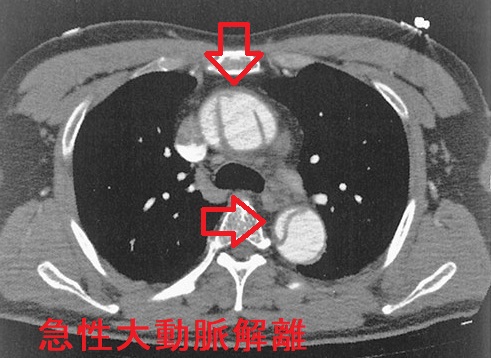

急性大動脈解離(acute aortic dissection: AAD)とは、大動脈壁の脆弱さ、動脈硬化、高血圧などが原因で生じます。血管内膜に亀裂が入り、中膜が裂け、内腔側が内膜フラップ(intimal flap)になって、その下に偽腔が生じる病態です。

急性大動脈解離(AAD)の症状は、前胸部から裂けた箇所[喉(のど)、背中、腰部など]に広がる突然の激しい胸痛、背部痛(70~80%)。9~20%は無痛性。「喉(のど)の痛み」が主症状(主訴)で軽い胸痛、背部痛だと、耳鼻咽喉科・内科・甲状腺専門医を受診して急性大動脈解離の診断が遅れる可能性があります。当然、甲状腺にも喉(のど)にも痛みの原因は無く、逆流性食道炎・非びらん性胃食道逆流(NERD)、狭心症による放散痛の除外診断目的で消化器内科、循環器内科を受診することになりますが、循環器内科を速やかに受診すれば急性大動脈解離を見つけられる確率は高くなります。

急性大動脈解離(AAD)では肺血栓塞栓症(肺梗塞)同様、血中Dダイマーが上昇します。